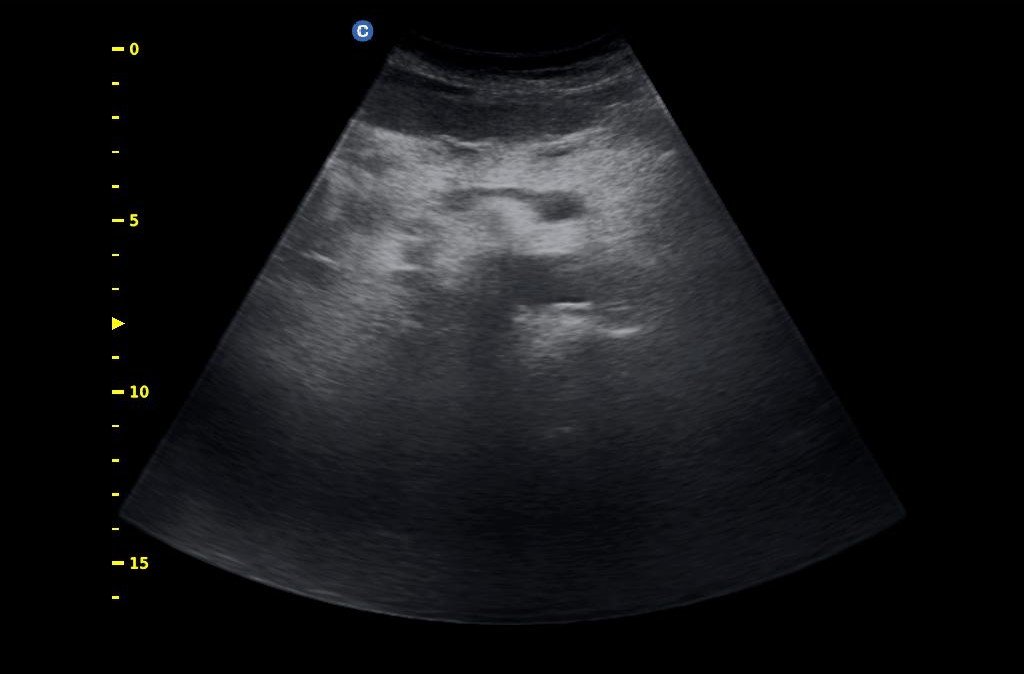

- Υπέρηχος άνω κοιλίας κατ’ οίκον ( ήπαρ, χοληδόχος κύστη, χοληφόρα, πάγκρεας, σπλην, νεφροί )

- Υπέρηχος άνω και κάτω κοιλίας κατ’ οίκον σε άντρα ( ήπαρ, χοληδόχος κύστη, χοληφόρα, πάγκρεας, σπλην, νεφροί, ουροδόχος κύστη, προστάτης)

- Υπέρηχος άνω και κάτω κοιλίας κατ’ οίκον σε γυναίκα ( ήπαρ, χοληδόχος κύστη, χοληφόρα, πάγκρεας, σπλην, νεφροί, ουροδόχος κύστη, μήτρα, ωοθήκες)